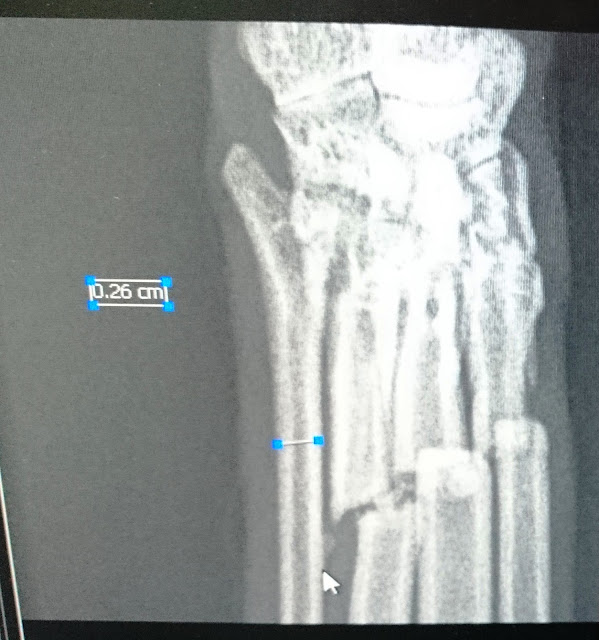

The six week

x-ray

The x-ray

after the operation

We took him to the vets, where they x-rayed him and found he had four

broken bones in what we would call his leg, but it is really his foot. They